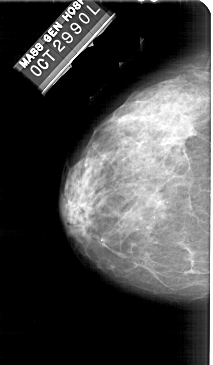

A_1949_1.LEFT_CC

LEFT_CC LINES 5101 PIXELS_PER_LINE 2971 BITS_PER_PIXEL 12 RESOLUTION 43.5 NON_OVERLAY